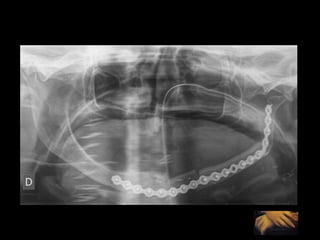

Adquisición de datos Reconstrucción virtual del modelo 3D Validación Validación Producción física del modelo Cirugía de modelo: moldeo placa, osteotomía mandíbula y peroné Esterilización: placa y modelo Uso en quirófano

Adquisición de datos Reconstrucción virtual del modelo 3D Validación Validación Producción física del modelo Cirugía de modelo: moldeo placa, osteotomía mandíbula y peroné. Esterilización: placa y modelo Uso en quirófano

Adquisición de datos Reconstrucción virtual del modelo 3D Validación Validación Producción física del modelo Cirugía de modelo: moldeo placa, osteotomía mandíbula y peroné, sistema relación. Esterilización: placa y sistema y modelo Uso en quirófano

Adquisición de datos Reconstrucción virtual del modelo 3D Técnica de espejo Validación Validación Producción física del modelo Cirugía de modelo: moldeo placa, osteotomía mandíbula y peroné. Esterilización: placa y sistema y modelo Uso en quirófano

Adquisición de datosReconstrucción virtual del modelo 3D Validación Validación Producción física del modelo Cirugía de modelo: moldeo placa, osteotomía mandíbula y peroné Esterilización: placa y modelo Uso en quirófano

Adquisición de datosReconstrucción virtual del modelo 3D Validación Validación Producción física del modelo Cirugía de modelo: moldeo placa, osteotomía mandíbula y peroné. Esterilización: placa y modelo Uso en quirófano

Adquisición de datosReconstrucción virtual del modelo 3D Validación Validación Producción física del modelo Cirugía de modelo: moldeo placa, osteotomía mandíbula y peroné, sistema relación. Esterilización: placa y sistema y modelo Uso en quirófano

Adquisición de datosReconstrucción virtual del modelo 3D Técnica de espejo Validación Validación Producción física del modelo Cirugía de modelo: moldeo placa, osteotomía mandíbula y peroné. Esterilización: placa y sistema y modelo Uso en quirófano